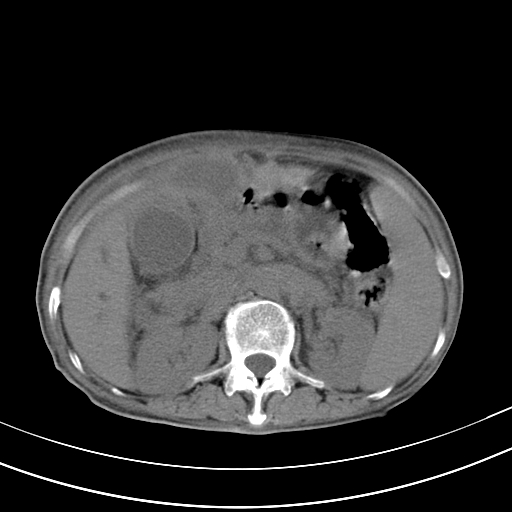

病人上腹部胀痛拌全身黄染八天

右侧少量胸水,胆囊增大,肝内胆管扩张,肝门部结构杂乱,建议增强。

肝内胆管及胰管扩张考虑为胰头区占位,肝门淋巴结增多,肝内多发低密度影,考虑为转移。门脉高压,脾大,胆囊大。

肝内胆管及胰管扩张,胰头增大考虑为胰头区占位,肝门淋巴结增多,考虑为转移。建议增强,脾大,胆囊大,壁厚,慢性胆囊炎。胃壁好像也增厚,且有一肿物。

胆囊增大,肝管扩张

脾大,

腹水,右胸腔少量积液。

胰腺炎。

1)考虑胰头癌并胆系低位梗阻;建议行ct增强扫描检查。2)慢性胆囊炎。3)脾大。4)少量腹水。5)双侧少量胸腔积液。